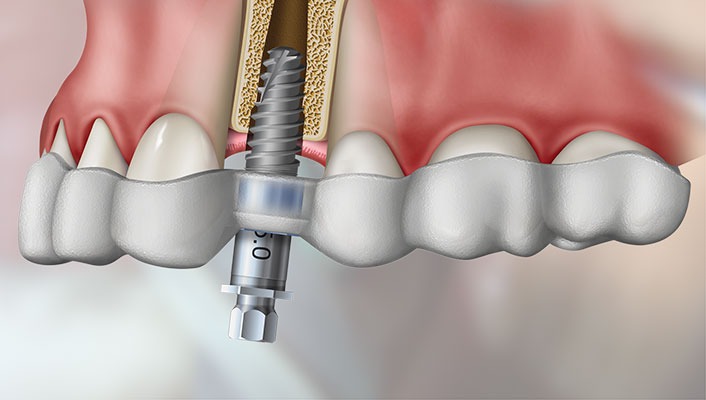

Implantes Dentários

Realizamos procedimentos de implantes dentários com segurança e precisão para sua saúde bucal.

Prótese Sobre Implantes

Prótese dentária é um dispositivo odontológico utilizado para substituir dentes ausentes ou danificados.

Cirurgia Guiada com Guias Empilháveis (Stackable Guide)

A técnica de cirurgia guiada com guias empilháveis (Stackable Guide) é uma inovação na implantodontia, proporcionando mais precisão, previsibilidade e segurança nos procedimentos

Consiste em um sistema de guias cirúrgicas que se sobrepõem (empilháveis), permitindo um planejamento digital detalhado e uma execução mais precisa da cirurgia